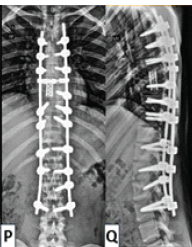

Multifocal Non-contiguous Spinal Tuberculosis: A Report of 3 Surgically-Treated Patients

Vibhu Krishnan Viswanathan , Malmarugan Ramachandran , Sathish Muthu , Gopalakannan Sivakumar , Annamalai Devadoss , Sathish Devadoss

………………………………p.176-182